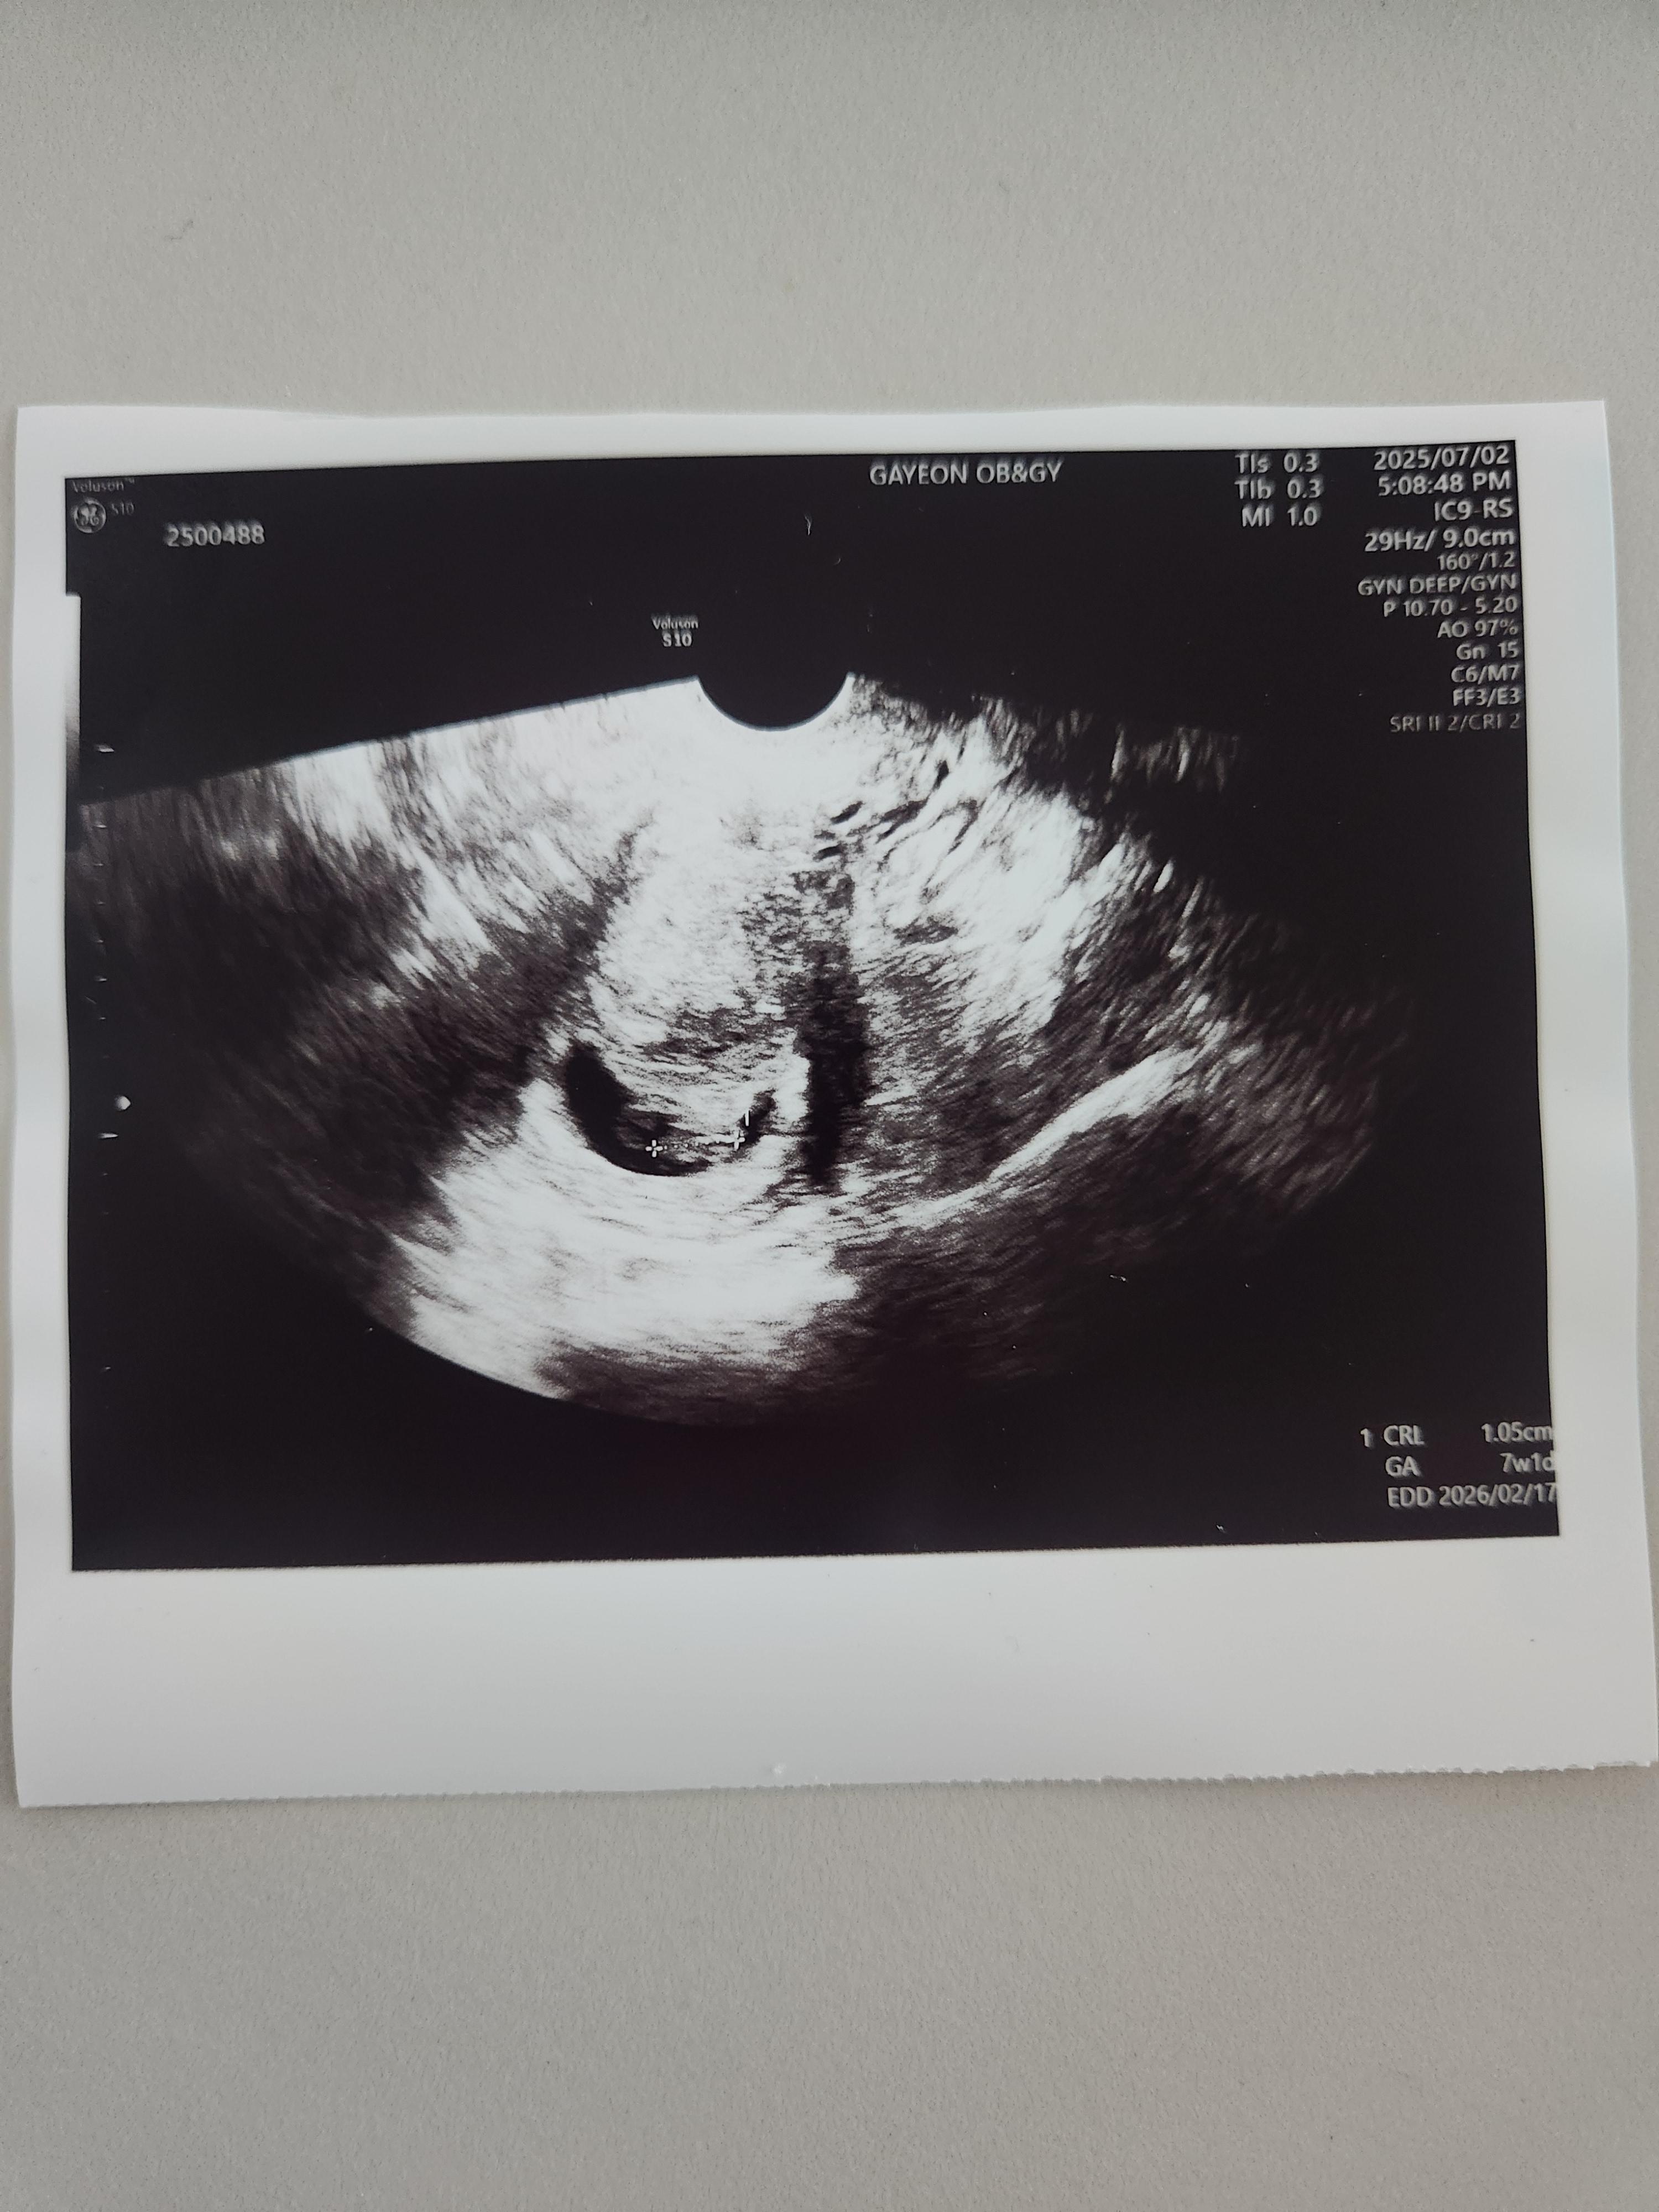

제가 7주 차에 아랫배가 찢어질듯한 쥐어짜는 듯한 통증을 느꼈다고 의사 선생님께 말씀드리고 초음파를 확인했습니다.

그런데 아기는 이상 없이 아주 잘 있었습니다.

제가 느낀 복통에 비해 아기는 너무나도 잘 있었고, 심장도 아주 잘 뛰고 있었습니다.

의사 선생님께서는 아기는 이상이 없는고 출혈도 없이 심한 통증을 느낀 거라면 아기집이 커지면서 나타난 통증일 것 같다고 하셨습니다.